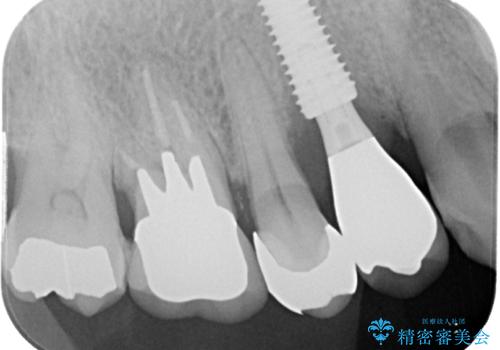

抜歯は避けたい? 1DAYインプラントに魅せられて抜歯即時埋入インプラントによる補綴治療

- 抜歯が必要なのでは?と近医で言われ、歯の保存を希望して来院された患者様です。

既に別の部位にインプラント治療を受けており、そのときの治療期間と苦労を鑑みて、何とか歯を残したいとのことで来院されました。

該当歯の状態としては何とか保存可能でしたが、予後不良のため、将来的にインプラント治療が必要となる可能性の高い状態でした。

当院での根管治療および歯周外科治療を併用した保存療法、並びに1DAYインプラントによる短期間インプラント治療の双方をご説明し、即日でインプラント治療を選択されました。

仮歯を用意した上で、抜歯即時埋入・即時荷重インプラントによる補綴治療を行うこととしました。